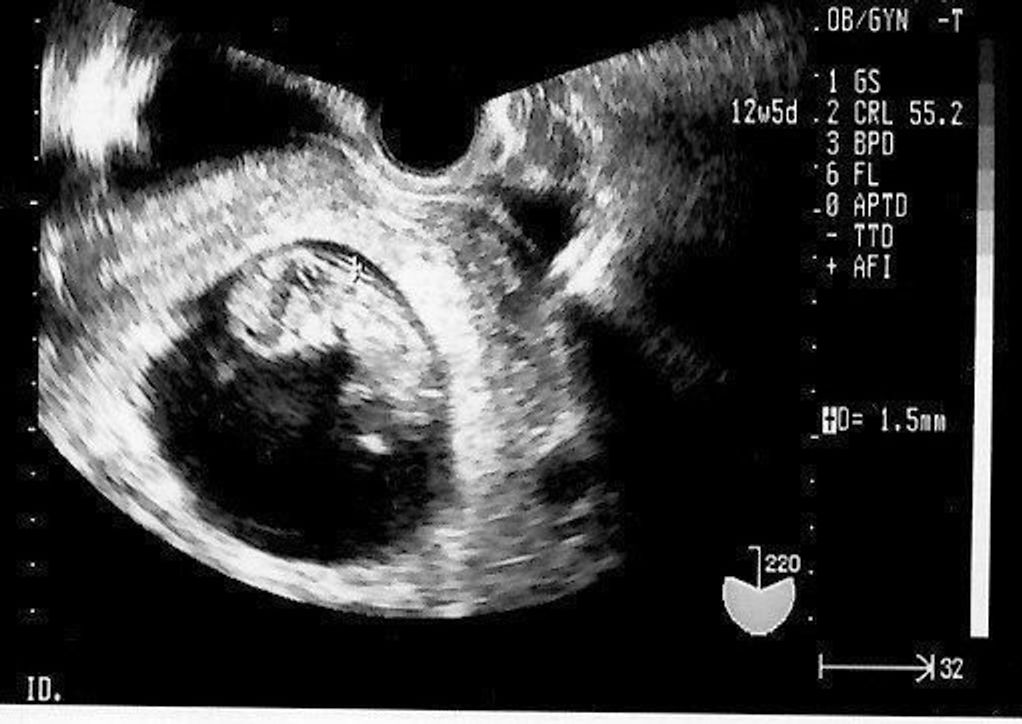

妊娠12週目 胎児の大きさ・体重・エコー写真、流産の可能性はかなり低く 妊娠12週(12w)になると今まで急成長を続けてきた赤ちゃんも、このあたりでペースダウン。 これから 妊娠12週目 赤ちゃんや子宮の大きさは?他にどんな症状が出るの? 妊娠・子育て よろず屋 妊娠12週目 赤ちゃんや子宮の大きさは?他にどんな症状が出る

妊娠初期(妊娠12~13週) 妊娠中期(妊娠14~15週)(4か月) 赤ちゃんの頭部・体重(妊娠15週) 頭部約3cm 体重約1g 赤ちゃんの様子 ・髪の毛が生え始め、身長がグンと伸び始める赤ちゃんこんにちは 妊娠中の生活 上手に乗り切ろう topへ わかりやすい妊娠週数一覧表 WHOが定めた妊娠週数です。ブックマークして分からない時の閲覧用にどうぞ。 胎児の変化 母胎の変化妊娠4か月の変化と過ごし方 妊娠4か月(妊娠12~15週)に入ると、つわりが収まって流産の危険性も下がります。 妊娠によって一時的に上昇した基礎体温は下がってきて平熱に戻ります。 おなか